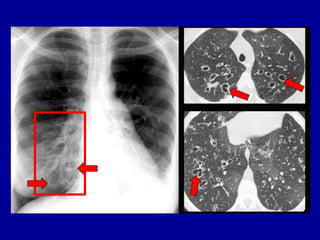

DOENÇAS DIFUSAS

PULMONARES

• RADIOGRAFIAS: TEM LIMITAÇÕES PARA A

CARACTERIZAÇÃO DESTAS LESÕES

• TC DE ALTA RESOLUÇÃO:

– DIAGNÓSTICO DIFERENCIAL

– CONTROLE EVOLUTIVO

– DEFINIR LOCAIS PARA BIÓPSIA

RADIOGRAFIA:

INFILTRADO RETICULAR

NA BASE E PERIFERIA

PULMONAR

PADRÃO

RETICULAR

NODULAR